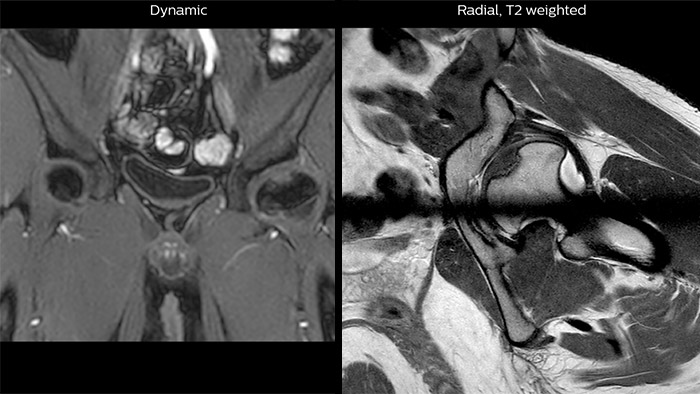

Crohn’s disease in the terminal ileum A large abscess is visible near the terminal ileum, in the middle of the coronal image.

Perthes disease in left hip The affected area on the upper circumference of the left hip shows contrast uptake in the dynamic scan. The radial scan nicely depicts the hip area, despite the dark shape in the center that is inherent to the radial way of scanning.